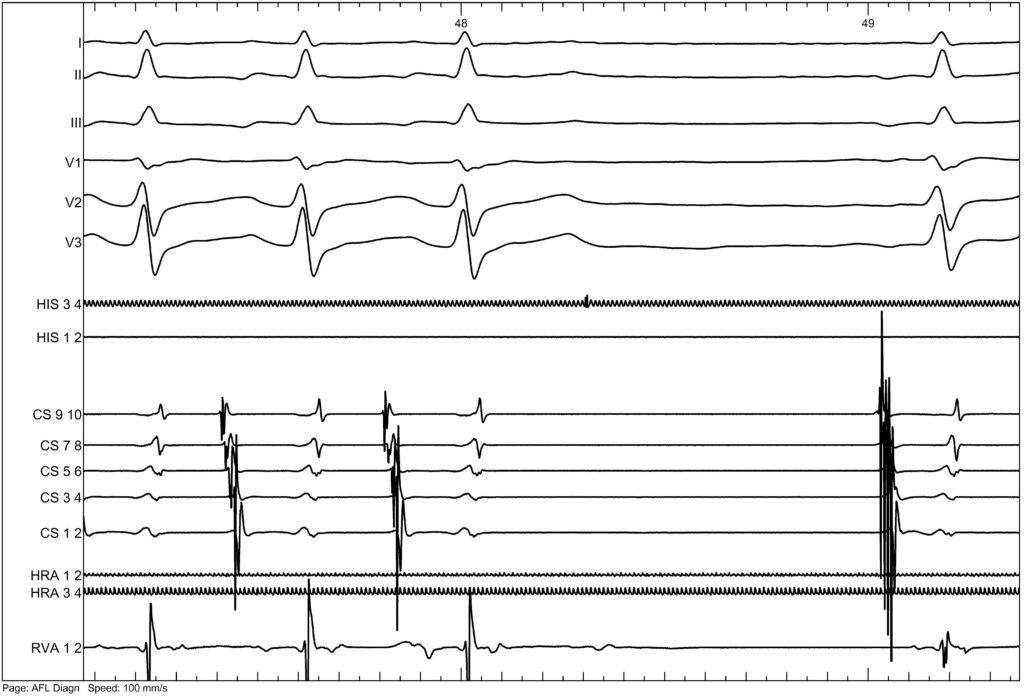

This is a 60-year-old patient presenting with palpitations. He had previously undergone an electrophysiological study four years ago. During that study, the following tachycardia was induced.

The tachycardia terminated with a ventricular beat

Here, we were not able to perform overdrive pacing, but since the tachycardia terminated each time with a ventricular beat, we concluded that this was a slow–slow AVNRT.